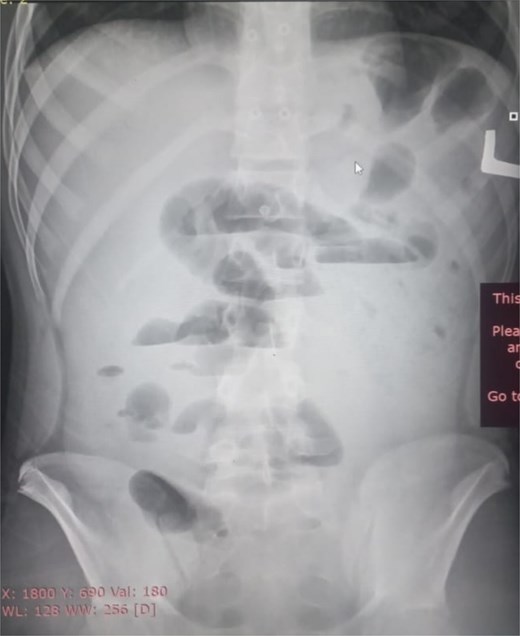

Initial radiographic evaluation with a plain abdominal X-ray confirmed the clinical suspicion of acute intestinal obstruction, demonstrating multiple air-fluid levels and diffuse small bowel dilatation (Fig. 1). To further delineate the underlying etiology, a contrast-enhanced computed tomography (CECT) scan was performed; providing critical diagnostic information it revealed, in the right iliac fossa, a striking encapsulation of the small intestine loops within a sac-like membrane, accompanied by ascites. This constellation of findings formed a pathognomonic cocoon-like structure (Fig. 2). Furthermore, the CECT identified a concurrent gut malrotation, evidenced by a left-sided displacement of the colon (Fig. 3). Laboratory findings showed an elevated total leukocyte count (TLC) of 21 000, indicative of inflammation, while other parameters were within normal limits. The patient underwent an exploratory laparotomy. Intraoperatively, the abdominal viscera were encased within a thick fibrous membrane (Fig. 4), containing ascitic fluid. The membrane was incised, adhesiolysis was performed, and the entrapped small bowel loops were released, and then a kink in the small intestine causing obstruction was identified and corrected. Additionally, the appendix was found to be secondarily involved in the encapsulating process. It was encased in the dense fibrocollagenous membrane, forming an inflammatory mass consistent with chronic serositis and localized fibrosis, rather than a classic acute appendicular phlegmon. Based on this intraoperative assessment that the mass was a manifestation of the cocoon’s chronic inflammation, a simple appendectomy was performed instead of a more extensive right hemicolectomy. This procedure was necessary to achieve complete release of the entrapped bowel, remove this localized inflammatory focus, and obtain a specimen for histopathology to definitively rule out a primary appendiceal pathology as a secondary cause of the peritonitis. Furthermore, ascitic fluid analysis showed no bacterial or mycobacterial growth, ruling out tuberculosis and the histopathological examination confirmed the fibrocollagenous nature of the membrane. The patient recovered well postoperatively and was discharged on the sixth day with advice for a follow-up after 2 weeks. At the follow-up visit, he reported no symptoms, and abdominal imaging confirmed the absence of obstruction. Histology further confirmed the benign fibrous nature of the membrane, with no signs of malignancy.

Axial CT demonstrating key pathological features. This contrast-enhanced axial view shows the colon displaced to the left side of the abdomen, confirming the presence of gut malrotation. The centrally clustered small bowel loops are seen encased in a dense sac, forming the characteristic cocoon structure that is pathognomonic for abdominal cocoon syndrome.